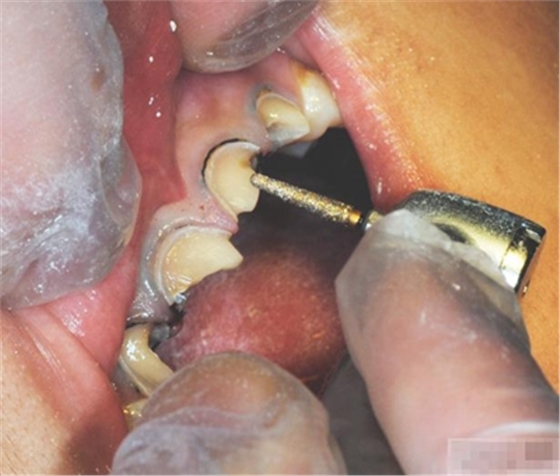

選擇合適的完成鉆制備根管,

通常深入到根管的1/2至2/3處

【纖維樁制作】

修整纖維樁長(zhǎng)度

取出纖維樁,按所需長(zhǎng)度裁截纖維樁 在有水條件下 用切割砂片或車針截取纖維樁,切勿使用鉗子,剪刀或鑷子以免破壞樁的結(jié)構(gòu)